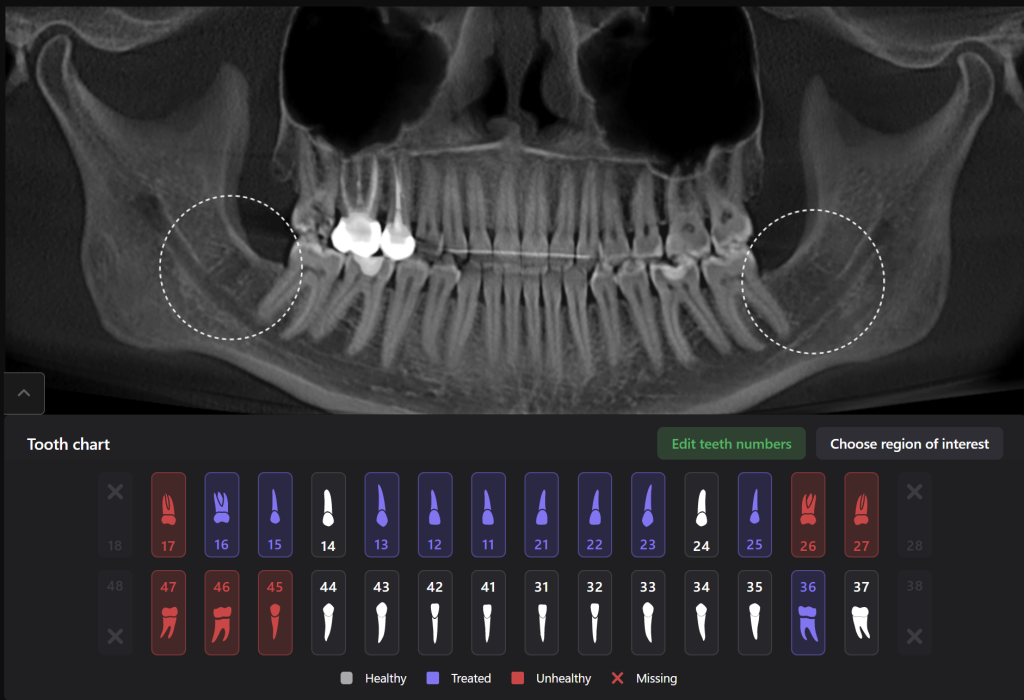

Diagnocat AI will help you carefully plan your procedure, such as the removal of teeth 38 (Universal 17) and 48 (Universal 32), minimizing the risk of possible complications

The 3D reconstruction from CBCT data (STL report Diagnocat) is a convenient tool for determining the level of complexity of the upcoming surgical procedure

It also serves as a visualization tool during communication with the patient

Teeth 38 (Universal 17) and 48 (Universal 32) were extracted with minimal surgical trauma and without causing damage to the inferior alveolar nerve